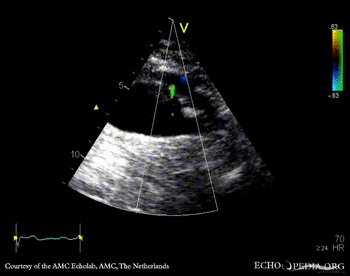

Aortic dissection type A

A3CH A3CH with Color Doppler: mild aortic regurgitation